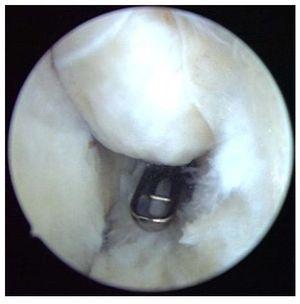

Fig. 10 Después de la sinovialectomía se extraen los cuerpos articulares libres. Según el tamaño de estos cuerpos, la extracción se realizará mediante pinzas o un resector sinovial.

Fig. 11 a, b) Los osteofitos en la zona del proceso coronario se extraen con un cincel Lambotte. c) Los fragmentos osteocondriales se extraen de la articulación con una pinza de agarre. d) El proceso coronoides remanente se alisa con el resector sinovial o una fresa de bola (no representado en la imagen).